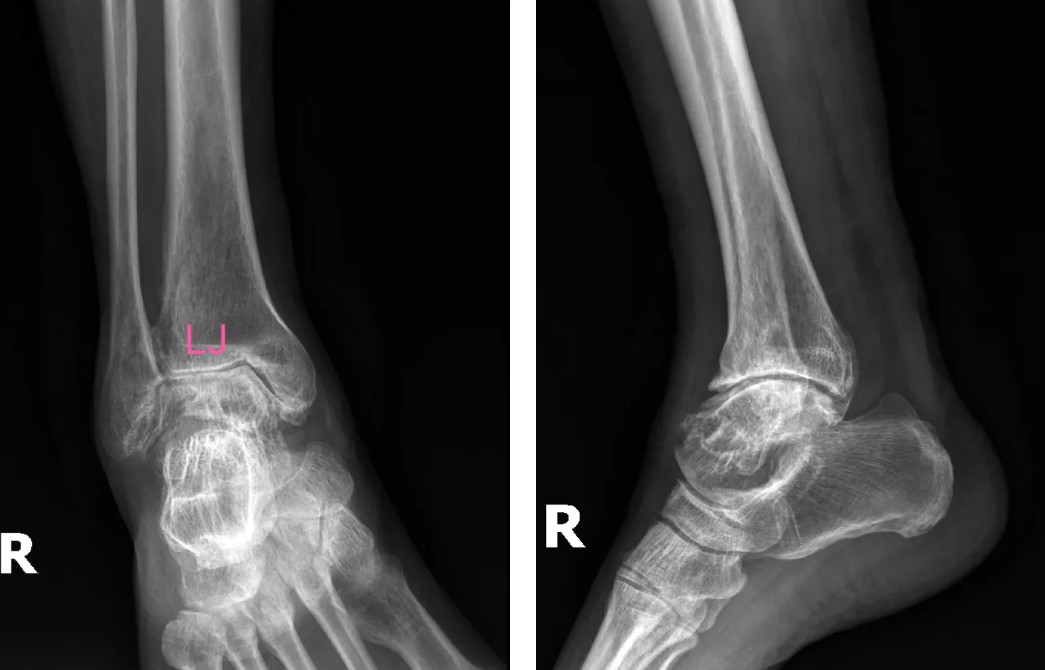

術(shù)前影像

患者吳先生(66歲)雙踝關(guān)節(jié)疼痛、活動(dòng)受限長(zhǎng)達(dá)10余年,保守治療無效后,關(guān)節(jié)逐漸畸形腫脹,連正常走路都成了奢望。廣安醫(yī)院副院長(zhǎng)、關(guān)節(jié)科主任羅軍副主任醫(yī)師團(tuán)隊(duì)經(jīng)全面評(píng)估,決定采用3D打印定制化人工全踝關(guān)節(jié)置換術(shù)。